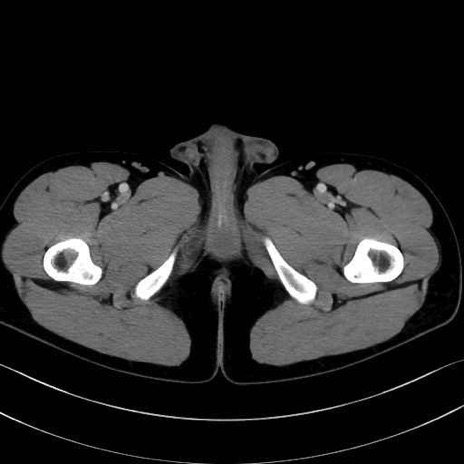

外閉鎖筋 (Obturator externus)